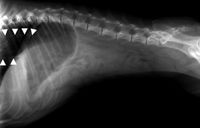

Esophageal diseases, including megaesophagus, can easily sneak up on the unsuspecting clinician if regurgitation, the cardinal sign of esophageal disease, is not considered a differential diagnosis for an animal that presents for what the owner perceives as vomiting.

Esophageal foreign bodies and esophagitis have the potential, if not identified and treated, to cause esophageal strictures or megaesophagus, which can be more difficult to treat.

Are contrast studies still needed as diagnostics in vomiting patients?